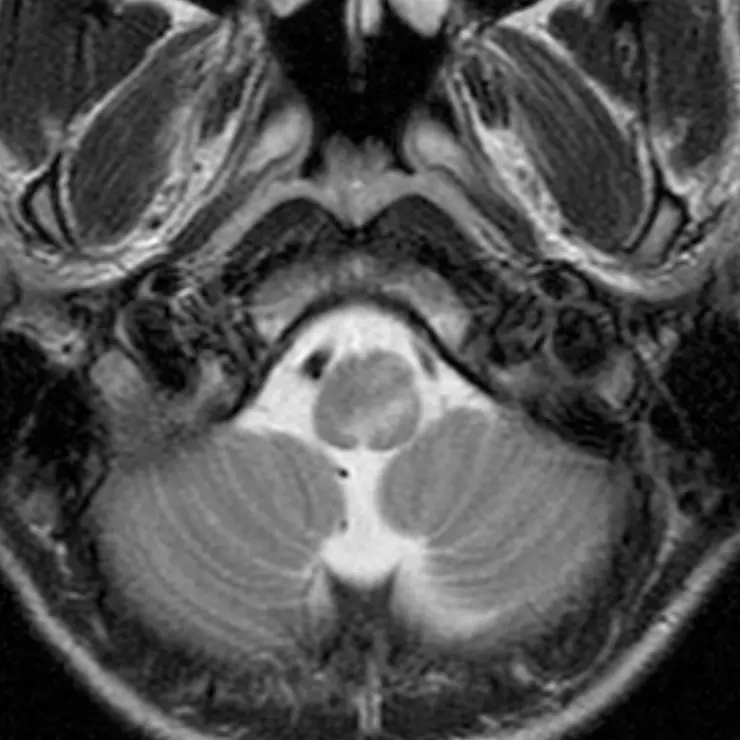

The pons' bulbous contour in the sagittal plane can also be seen on axial cuts. The "Mickey Mouse" appearance of the midbrain is no longer visible.

1. Fourth ventricle

The triangular CSF space posterior to the pons is the fourth ventricle. It should be seen on every head CT or brain MRI and, if it is not, there is likely pathology. Effacement of the fourth ventricle may be an early sign of mass effect, either due to a lesion or edema.

2. Basilar artery

The basilar artery courses along the surface of the pons. It should always be dark on a T2-weighted image. A bright basilar artery is a sign that blood has stopped moving or is moving slowly (i.e. "loss of flow void"), suggesting an occlusion.

View the images on the right to see how the caliber of the fourth ventricle changes as you scroll up and down. The fourth ventricle's caliber is largest at the mid aspect of the pons.